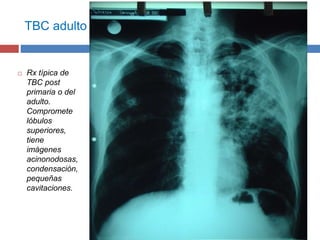

TBC adulto

 Rx típica de

TBC post

primaria o del

adulto.

Compromete

lóbulos

superiores,

tiene

imágenes

acinonodosas,

condensación,

pequeñas

cavitaciones.

• #18 Rx típica de TBc post primaria o del adulto. Compromete lóbulos superiores, tiene imágenes acinonodosas, condensación, pequeñas cavitaciones.